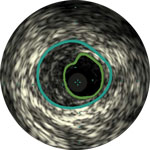

Behandlungsplan Beispiel 1

Lumen

Exzentrische fibröse Plaque mit tiefliegendem Calcium

Schallschatten

Gefäßgröße: 5,5 mm Durchmesser Plaquemorphologie: fibröse Plaque mit intimalem und mittlerem Calcium Plaquegeometrie: exzentrische Läsion Position des Führungsdrahtes: wahres Lumen

Quick-Cross-Katheter: souverän komplexe Morphologien durchqueren Direktionale Atherektomie mit Phoenix: frontal zum Schneiden, Erfassen und Freilegen gemischter Morphologien, einschließlich Kalzium; Möglichkeit der Richtungssteuerung für größeren Lumengewinn AngioSculpt Scoring-Ballonkatheter: Calcium messen, um eine Dissektion zu reduzieren4 Stellarex DCB: entwickelt für hohe Leistungsfähigkeit bei Kalzifizierungen

Erleichtert die Dimensionierung des Geräts, um eine präzise Wandapposition, Medikamentengabe und Platzierung sicherzustellen

Verstehen Sie Art und Schweregrad der Plaque, um das richtige Gerät zu wählen

Visualisieren Sie die Position der Plaque für eine präzise Behandlung

Bestätigen Sie die Position des wahren Lumens oder des subintimalen Führungsdrahts